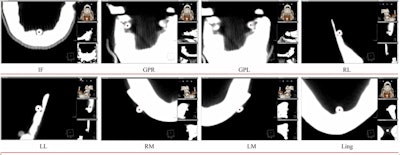

Eight landmarks placed on the DICOM image slice and viewed in 3D: (A) Incisive foramen (IF). (B) Greater palatine right foramen (GPR). (C) Greater palatine left foramen (GPL). (D) Right lingual foramen (RL). (E) Left lingual foramen (LL). (F) Right mental foramen (RM). (G) Left mental foramen (LM). (H) Lingual tubercle (LING). Almukhtar A, Khambay B, Ayoub A, et al. (2015) "Direct DICOM Slice Landmarking" A Novel Research Technique to Quantify Skeletal Changes in Orthognathic Surgery. PLOS One 10(8): e0131540. doi:10.1371/journal.pone.0131540.